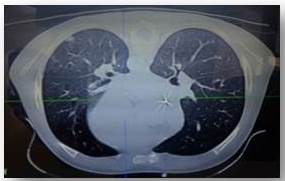

Se trata de escolar masculino de 6 años de edad, natural de Acarigua, (Venezuela) con antecedentes de Diabetes Mellitus Tipo 1 (no tratada), cuya madre refiere inicio de enfermedad actual el día 28/06/2017 al presentar dolor abdominal, difuso, de moderado a fuerte intensidad de carácter urente, concomitante distención abdominal, inapetencia, por lo es evaluado por gastropediatra el cual indica tratamiento sintomático y enema evacuante, para el día 01/07/2017 se asocia a cuadro emesis en n° 03 de contenido bilioso fétido; motivo por el cual es referido a centro hospitalario en San Carlos Cojedes (Venezuela) donde es evaluado y se deciden su ingreso bajo la premisa de: 1. Abdomen agudo inflamatorio 2. Íleo paralítico 3. Hernia inguinal derecha. Es llevado a mesa operatoria, se practica incisión para rectal derecha, apertura de peritoneo, aspiración de líquido claro, localización de masa tumoral, infiltrando techo de vejiga, ciego, epiplón, íleo distal, resección de epiplón (ganglionar) de coloración rosada y de ganglios mesentéricos, tumoración de techo de vejiga de aspecto hemorrágico, necrótico. Para el (25/07/2017) se recibe resultado de biopsia con diagnósticos de inmunohistoquímica para linfoma tipo burkitt cd20+, cd10+ en el 95 % de las células tumorales se le realizan a su vez estudios de extensión (28/07/17) que reportan: TAC DE TÓRAX: foco de condensación en el tercio medio y anterior del pulmón izquierdo y en las bases pulmonares , TAC ABDOMEN Y PELVIS: localización de masa tumoral, infiltrando techo de vejiga, ciego, epiplón, íleo distal, LÍQUIDO CEFALORRAQUÍDEO: sin evidencia de neoplasia, ASPIRADO DE MÉDULA ÓSEA: sin evidencia de neoplasia. En vista de hallazgos se cataloga (ESTADIO II) GRUPO B, por lo que se programa para quimioterapia sistémica: recibe esquema COP (25/07/17) (ciclofosfamida, vincristina,predinisona,e intratecal con metotrexate) con re-evaluación de sitios de enfermedad con respuesta completa, COPADM-1 (ciclofosfamida, adriamicina,metotrexate,vincristina,prednisona) (02/08/17) con una segunda evaluación con respuesta completa, COPADM-2 (vincristina, metotrexate,intratecal con metotrexate e hidrocortisona) (29/08/17): con re-evaluación de TAC de tórax, abdomen y pelvis, sin evidencia de neoplasia. En vista de la respuesta clínica >90 % se programa para su 1er ciclo de consolidación con quimioterapia con CYM el cual cumple por 6 días con excelente respuesta clínica, se le toma líquido cefalorraquídeo posterior a tratamiento con intra-tecal el cual se reporta a los 10 días de su toma positivo para infiltración neoplásico se interconsulta caso con hemato-oncólogos pediatras quienes sugieren intra-tecal triple con (metrotexate-citarabina-hidrocortisona) que se realizó en 3 oportunidades y realizar prueba específica citometría de flujo, la cual se realiza con posterior reportes de líquidos negativos para infiltración neoplásica. En vista de tal escenarios se decide pasar a GRUPO C y recibe su 1er ciclo de quimioterapia con CYVE-1 (citarabina,etopósido y metotrexate) + INTRATECAL el cual posterior a los 10 días en el nadir de su terapia hace toxicidad hematológica con contajes absolutos de neutrófilos <100 por lo recibe antibioticoterapia de amplio espectro. Se le realizan estudios de evaluación tipo TAC de tórax donde llama la atención nódulos pulmonares presentes en área mediastínica (4 en total) con paquipleuritis bilateral (Figura 1,2,3) bajo la sospecha de infección oportunista por estado de inmunosupresión se inicia tratamiento con anti fúngico tipo Anfotericina B y se le indican realizar estudio de galactomanano para descartar aspergilos por la asociación de la misma con LNH ( no se realiza por no haber reactivos en nuestro país) se discute caso con infectólogo pediatra quien menciona mantener Anfotericina B por 21 días en vista de que paciente presenta mejoría clínica y desde el punto de vista tomográfico ( se le logra realizar estudios micológico en la Universidad Central de Venezuela) se recibe resultado de frotis de sangre (examen micológico) que reporta positivo para Histoplasma Capsulatum.